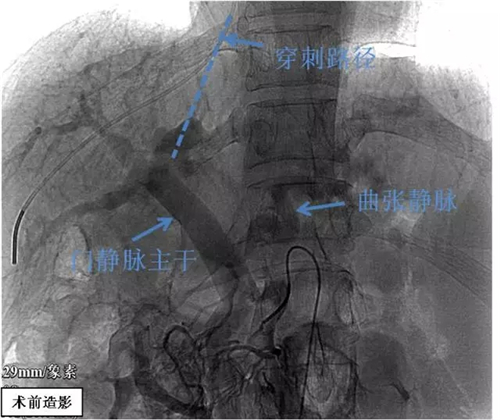

经颈静脉肝内门体分流术(transjugularintrahepatic portosystemic shunt,TIPS),是指经颈静脉入路从肝静脉穿刺肝内门静脉,在肝静脉与门静脉之间建立门-体分流道,以达到降低门静脉压力、治疗食管胃静脉曲张破裂出血和顽固性腹腔积液等一系列门静脉高压并发症的微创介入治疗技术。

案例分享:47岁的赵先生,1年前发现患有丙肝肝硬化,未规律抗病毒治疗。1年前曾因“胃底静脉曲张破裂出血”于外院行肽夹止血治疗。此次入院前6小时无明显诱因出现呕血约400ml,入院前2小时再发呕血,量约300ml。急诊收入我院,考虑“肝硬化伴食管胃底静脉曲张破裂出血”可能,三腔二囊管压迫止血无效,遂行经颈内静脉门体分流术。(王森)